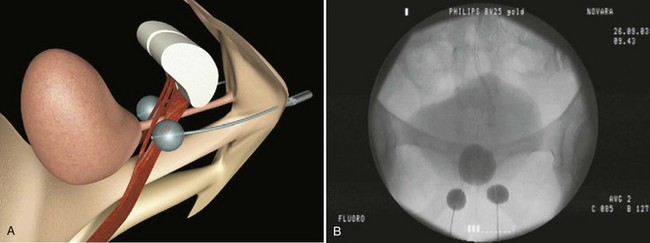

The Adjustable Continence Therapy (ACT) device (Uromedica, Plymouth, MN) consists of two inflatable silicone balloons attached to silicone tubing with a titanium and silicone port (Fig. 74–8). The procedure can be done under local, regional, or general anesthesia. The balloons are placed into the periurethral space at the bladder neck with introducer devices inserted through two 1-cm incisions in the labial sulci at the level of the vaginal introitus. The procedure is carried out under fluoroscopic guidance with a contrast-filled Foley balloon positioned at the bladder neck. After the correct position is ascertained the device balloons are inflated with 1.0 to 1.5 mL of an isotonic solution (sterile water and contrast material).The aim is to increase urethral resistance and support the bladder neck with the inflated balloons (Stecco et al, 2006). The ports are buried in the subcutaneous tissue of the labia to enable postoperative reinjection of the balloons if necessary (Kocjancic et al, 2008). Beginning at 6 weeks, additional fluid, usually with volumes of 2 mL, can be added to the balloons by injecting percutaneously through the port sites, if necessary. The technology was developed as an alternative to bulking agents that would not migrate (Kocjancic et al, 2008).

Figure 74–8 Illustration of Adjustable Continence Therapy balloon device for women. A, Schematic diagram showing percutaneous placement of the balloons on both sides of the bladder neck. B, Fluoroscopic picture showing contrast agent in the bladder, Foley catheter, and balloons.

(From Aboseif SR, Franke EI, Nash SD, et al. The adjustable continence therapy system for recurrent female stress urinary incontinence: 1-year results of the North America Clinical Study Group. J Urol 2009;181[5]:2187–91.)

Kocjancic and coworkers (2008) implanted 49 patients, of whom 38 were observed for more than 1 year. Of these, 26 of 38 (68%) were dry, 6 of 38 (16%) were improved, and 6 of 38 (16%) experienced failure. In 62%, one to five fluid additions were necessary throughout the follow-up period. Wachter and coworkers (2008) reported a series of 41 women: the dry rate was 44%, marked improvement was 15%, and 41% had slight improvement or no change; device adjustment was need in 70% of patients. Aboseif and coworkers (2009) reported a North American study consisting of 162 patients of whom 84% had undergone at least one unsuccessful surgical procedure for SUI. Of those observed for 1 year or more, 107 of 140 (76.4%) improved by one or more Stamey grades, 67 of 130 (52%) had less than 2 g of urine on pad weight testing, and 102 of 126 (81%) had a greater than 50% reduction in provocative pad weight. Within 9 months of implantation a mean of 2.3 balloon readjustments were required. Because volume adjustments were done during the follow-up periods in all series there were no data available on continence outcome long after cessation of fluid addition.